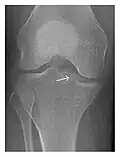

The greater tuberosity of the humerus is also an illustrative location of occult fractures. The osseous injury may follow seizures, glenohumeral dislocation, forced abduction, or direct impaction. They are commonly discovered on MRI in symptomatic patients with suspicion of rotator cuff tear. Coronal images are best suited for detection. They appear as crescentic oblique lines surrounded by a bone marrow edema pattern (Figure 5). The rotator cuff must be inspected since associated ligamentous lesions are common. In the ankle, malleoli and tarsal bones should be checked carefully for any cortical disruptions and radiolucent lines that may reveal a fracture. Awareness of the exact location of the pain will help direct the attention of the interpreter when searching for very subtle signs of fracture (Figure 6).[1]

Figure 6: Subtle anterior talar fracture in a 39-year-old man presenting with ankle pain after a fall. (a) Anteroposterior radiograph shows a subtle oblique radiolucent line through the talus (white arrows). (b) Sagittal CT reformation confirms the presence of an anterior talar fracture with cortical offset (black arrow). Avulsion fractures, which consist of a detached bone fragment resulting from a ligament or tendon pulling away from the bone, may also present with subtle radiographic signs. Tiny osseous fragments near the presumed attachment site of a ligament suggest this diagnosis. Common sites are the lateral tibial plateau (the Segond fracture), the spinal tuberosity of the tibia resulting from anterior cruciate ligament avulsion, and the ischial tuberosity.[1]